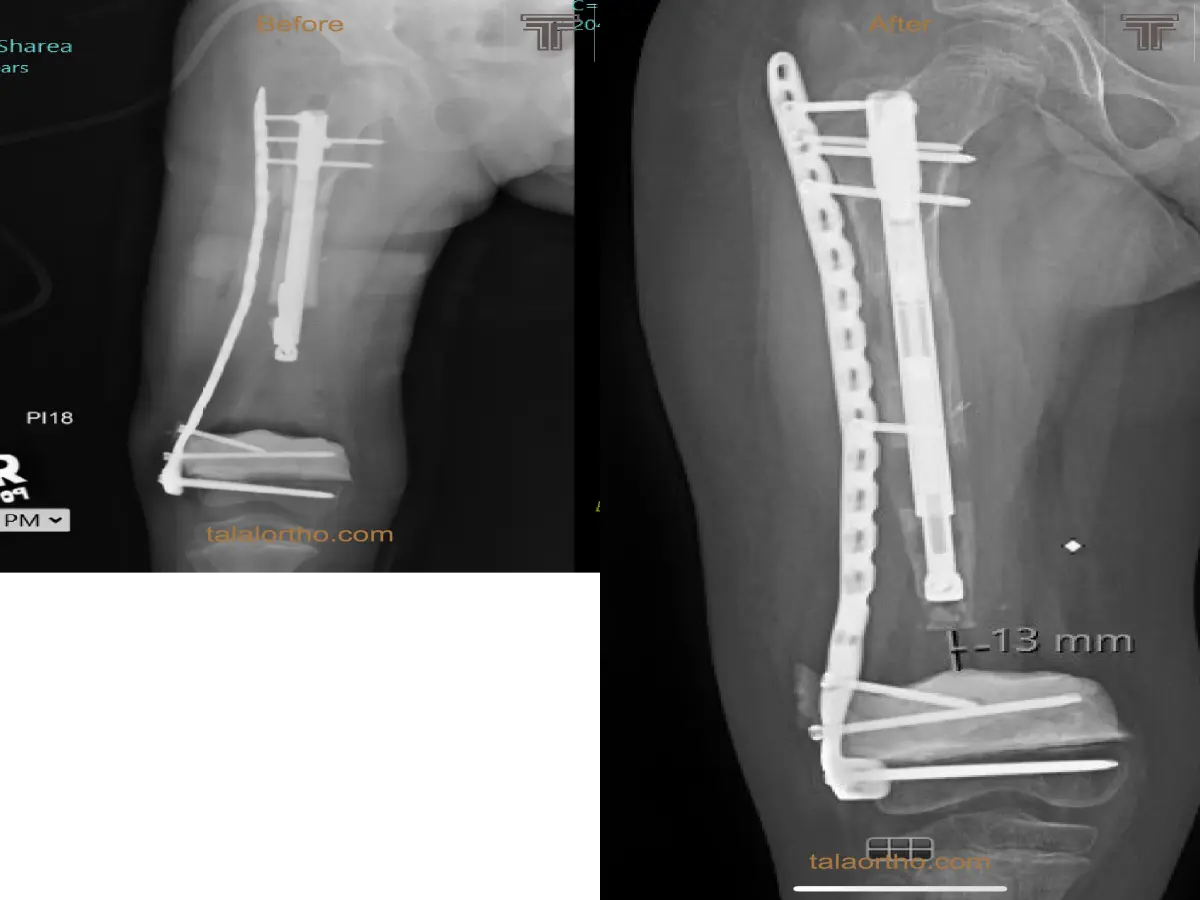

العظم الزجاجي هو مرض وراثي يؤدي الى كسور متعددة وتشوهات/تقوسات في العظام. تعالج الكسور في أول سنتين بالعادة بالجبس ...

بخلاف الكسور العادية في الاطفال فإن مثل هذا الكسر يحدث دون اصابه والتآمه صعب. في حال التآمه بعد التدخل الجراحي ...